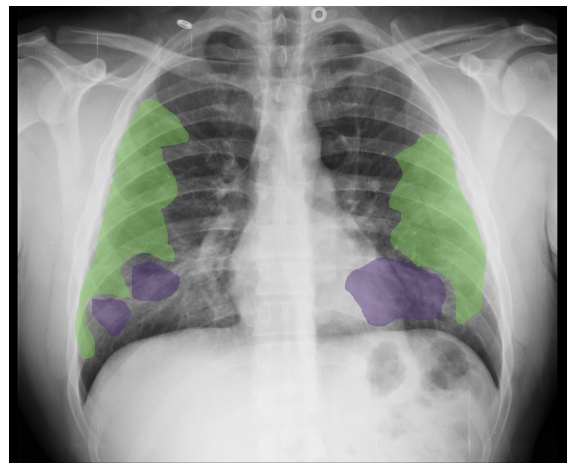

Annotation of regions of interest

Since some lesions such as infiltrates, ground glass opacities or consolidation patterns are the most frequent in COVID-19 patients, a sub-set of 10 images were annotated with their ROIs by a team of eight radiologists from the Hospital Universitario de San Juan de Alicante, for the first iteration of the BIMCV COVID-19+ dataset.

As it can be seen in Figure 3, ROIs corresponding to these findings were labeled at a pixel level using XNAT OHIF Viewer [25]. OHIF is a zero-footprint medical image viewer provided by the Open Health Imaging Foundation that stores an XML output with the ROI paths. This information of great value to train semantic segmentation networks, such as UNet [26], in order to extract characteristics such as the extension and exact location of the lesions. Table 4 shows the findings annotated at a ROI level.